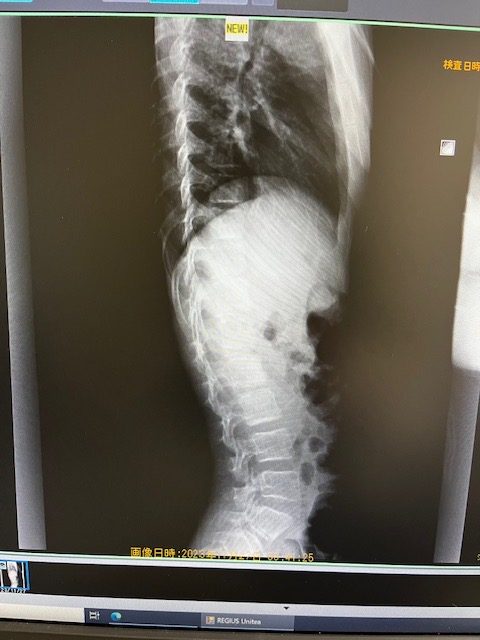

img03

2023年12月4日

Uploaded from お問い合わせ